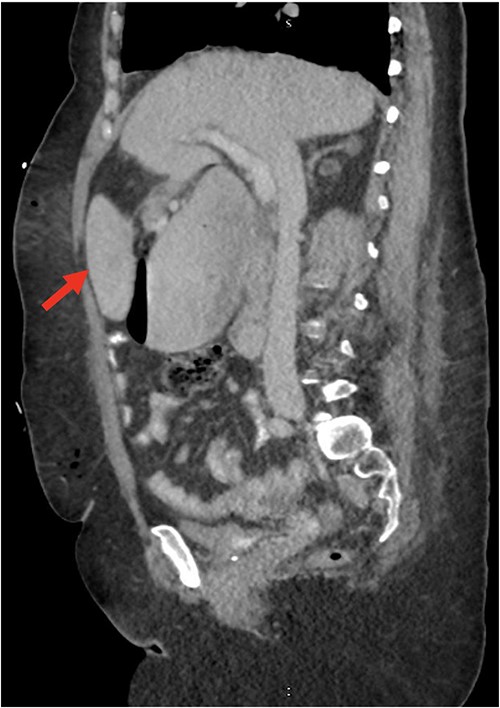

Despite the insertion of the NGT yielding 1500 cc output in 24 hours, the patient continued to experience severe abdominal pain. Urgent abdominal and pelvic computed tomography (CT) scans were taken, as seen in Figs 2–4. The CT scans showed gastric distension and the spleen positioned anteriorly in the right upper quadrant. Consequently, the decision was made to promptly bring the patient to the operating room for a diagnostic laparoscopy with plan to detorse the spleen.

CT of the abdomen and pelvis (coronal slice) showing gastric distention and the spleen positioned in the right upper quadrant.

Our patient’s pre-existing conditions presented challenges in distinguishing between expected postoperative discomfort and potential complications following her recent adrenalectomy. This uncertainty, combined with a normal WBC count, absence of fever, and regular bowel function, initially led the medical team to attribute her pain to the recent surgery two days prior, delaying her diagnosis and potentially exacerbating her condition. Subsequent imaging became imperative, revealing a persistent large gastric bubble despite NGT decompression, and malposition of the spleen (Fig. 3). This prompted immediate preoperative measures to facilitate a diagnostic laparoscopy.